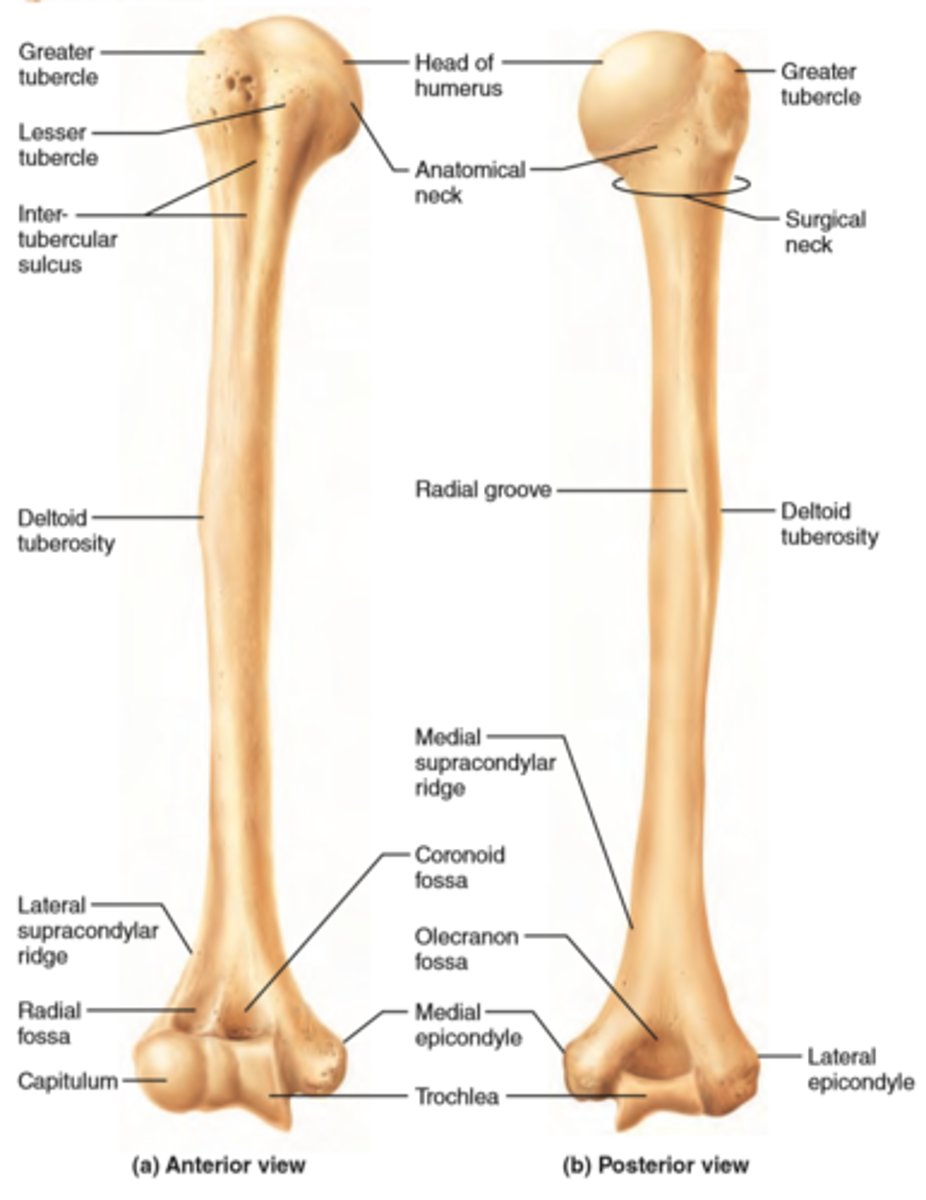

Features of the humerus:

- head

- anatomical nech

- surgical neck

- greater tubercle

- lesser tubercle

- intertubercular groove

- shaft

- deltoid tuberosity

- radial groove

- medial and lateral supra-epicondylar ridges

- condyle

- capitulum

- trochlea

- coronoid fossa

- olecranon fossa

Head of the humerus:

articulates with glenoid cavity of scapula

Anatomical neck of the humerus & its function:

- groove

- separates the head from the greater and lesser tubercles

- indicates the place of attachment of the glenohumeral joing capsule

Surgical neck of humerus:

- narrow part distal to head and tubercles

- common site of fracture!!!

Greater tubercle of humerus:

lateral position from head

Lesser tubercle of humerus:

anterior position from the head

Intertubercular groove of humerus:

- located between tubercles

- provides passage for the tendon of the long head of the biceps muscle

Shaft of the humerus:

long portion of the humerus with a tuberosity and a groove, engrossing distally

Deltoid tuberosity of humerus:

attachment for deltoid muscle

Radial groove of the humerus:

oblique demarcation on posterior side. Contains the radial nerve and deep artery of arm (named after the nerve)

Medial and lateral supra-epicondylar ridges of the humerus:

End distally as the medial and lateral epicondyles, involved in muscle attachment